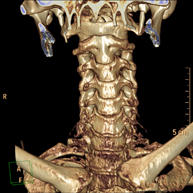

Prova radiològica que consisteix en obtenir imatges de les artèries caròtides del coll d'alta definició anatòmica, mitjançant l'ús d'un equip de TC (Tomografia Computeritzada) i la injecció de contrast intravenós. Posteriorment, les imatges són reconstruïdes en tres dimensions (3D). Indicacions: accident vascular cerebral agut, accident vascular transitori, buf cardíac. - TC Columna cervical

Prova radiològica que consisteix en obtenir imatges de les cervicals vertebrals d'alta definició anatòmica, mitjançant l'ús d'un equip de TC (Tomografia Computeritzada). Indicacions: cervicàlgia amb/ sense irradiació a braços, traumatisme.

- TC Columna cervical

Prova radiològica que consisteix en obtenir imatges de les vèrtebres cervicals d'alta definició anatòmica, mitjançant l'ús d'un equip de TC (Tomografia Computeritzada). Indicacions: dolor cervical amb/sense irradiació als braços, traumatisme, malformacions congènites. - TC Columna dorsal